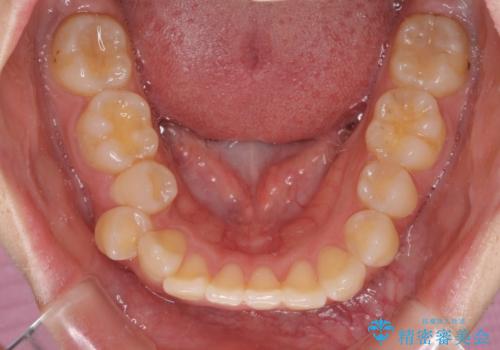

- 八重歯と口の閉じにくさを気にして来院された患者様です。

上下ともに前歯が前方に突出し、八重歯が唇に引っかかる感じもあり、口が閉じにくくなっていました。

上下左右の第一小臼歯4本を抜歯し、口元の突出感を改善しながら八重歯を解消していくこととしました。